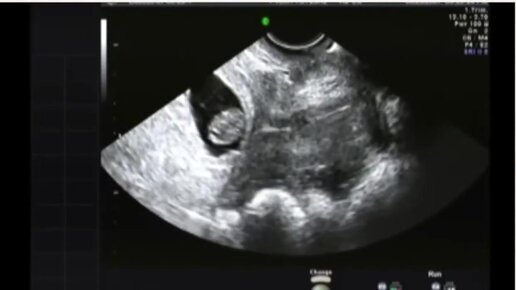

УЗИ на 8 неделе беременности

Медицинский женский центр